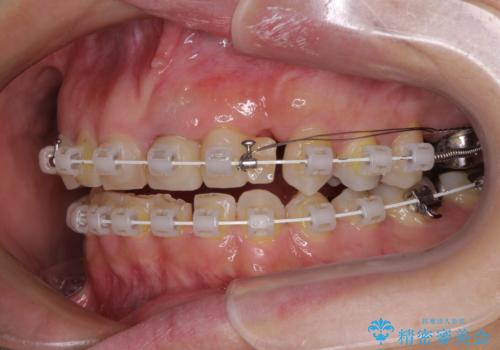

咬み合わせ改善のため、前歯の過剰歯を抜去し、ワイヤー矯正にて歯列と咬み合わせることとしました。

上下非接触の咬み合わせは、舌突出癖によるところが大きく、トレーニングを行いながら治療を進めていきました。

なかなか突出癖が改善できず、過剰歯を抜歯したスペースを閉じるまでに時間がかかりました。

舌突出癖の改善は、治療期間や仕上がりに大きな影響を与えるため、しっかりとトレーニングすることが大切です。